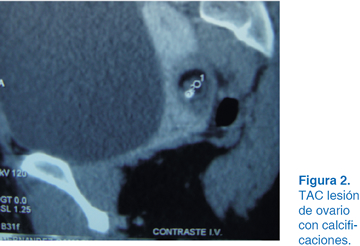

A los dos años del evento quirúrgico en el USG se apreció una tumoración en el ovario izquierdo con dimensiones de 10 x 12 cm (Figura 1). Se solicitó tomografía axial computarizada (TAC), observándose tumoración con densidades mixtas con diagnóstico probable de teratoma (Figura 2). Se optó por laparotomía exploradora donde se identificó el útero y se apreció tumoración dependiente de ovario izquierdo (Figura 3). Se realizó planeación de incisión (Figura 4), posteriormente tumorectomía (Figura 5) y salvamento de tejido ovárico (Figura 6). El reporte transoperatorio mostró teratoma monofásico con bordes libres de tumor.